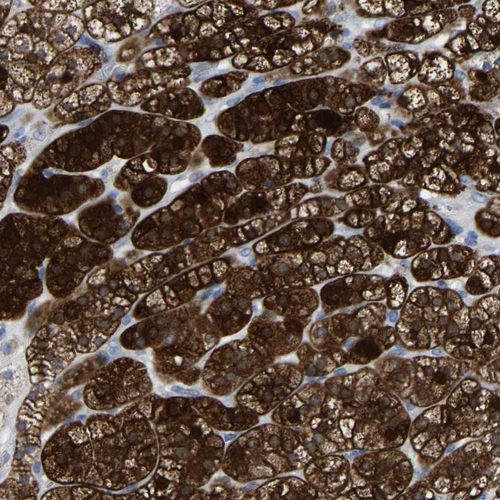

Immunohistochemical staining of human adrenal gland shows strong cytoplasmic positivity in cortical cells.